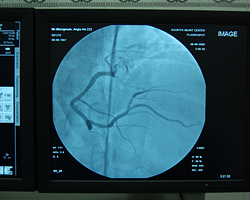

Cardiac Cath Lab

The Cardiology lab department is equipped with Siemens machine with the facilities for angioplasty both coronary and pherepheral, permanent pacemaker implantation and ICD implantation, which is operated by qualified professionals intensively focused on their own sphere of service.

Cardiac Cath Lab Inauguration Pictures